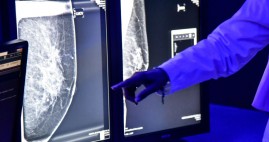

Nacional.-

Ya es oficial: la Cofepris advierte que los implantes mamarios de Allergan pueden causar cáncer |

| En conjunto con dicha empresa, la dependencia determinó llevar a cabo el retiro voluntario del mercado de los implantes mamarios texturizados y expansores d... 2019-07-31 17:12:56 |